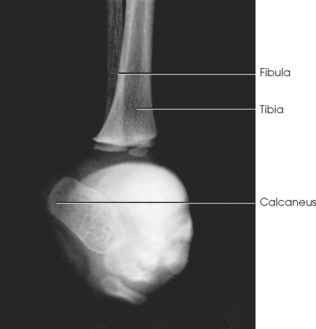

The foot consists of 26 bones (Figs. 6-1 and 6-2):

The bones of the foot are similar to the bones of the hand. Structural differences permit walking and support of the body’s weight. For descriptive purposes, the foot is sometimes divided into the forefoot, midfoot, and hindfoot. The forefoot includes the metatarsals and toes. The midfoot includes five tarsals—the cuneiforms, navicular, and cuboid bones. The hindfoot includes the talus and calcaneus. The bones of the foot are shaped and joined together to form a series of longitudinal and transverse arches. The longitudinal arch functions as a shock absorber to distribute the weight of the body in all directions, which permits smooth walking (see Fig. 6-2). The transverse arch runs from side to side and assists in supporting the longitudinal arch. The superior surface of the foot is termed the dorsum or dorsal surface, and the inferior, or posterior, aspect of the foot is termed the plantar surface.

The proximal foot contains seven tarsals (see Fig. 6-1):

Beginning at the medial side of the foot, the cuneiforms are described as medial, intermediate, and lateral.

The talus, irregular in form and occupying the superiormost position of the foot, is the second largest tarsal bone (see Figs. 6-1 to 6-3). The talus articulates with four bones—tibia, fibula, calcaneus, and navicular bone. The superior surface, the trochlear surface, articulates with the tibia and connects the foot to the leg. The head of the talus is directed anteriorly and has articular surfaces that join the navicular bone and calcaneus. On the inferior surface is a groove, the sulcus tali, that forms the roof of the sinus tarsi. The inferior surface also contains three facets that align with the facets on the superior surface of the calcaneus.

The cuboid bone lies on the lateral side of the foot between the calcaneus and the fourth and fifth metatarsals (see Fig. 6-1). The navicular bone lies on the medial side of the foot between the talus and the three cuneiforms. The cuneiforms lie at the central and medial aspect of the foot between the navicular bone and the first, second, and third metatarsals. The medial cuneiform is the largest of the three cuneiform bones, and the intermediate cuneiform is the smallest.

The joints of the lower limb are summarized in Table 6-1 and shown in Figs. 6-11 and 6-12. Beginning with the distalmost portion of the lower limb, the articulations are as follows.

Fig. 6-12 A and B, Joints of right foot. C, MRI sagittal plane of anterior foot. D, MRI sagittal plane of posterior foot and ankle. Joint spaces and articular surfaces are clearly shown.

The interphalangeal (IP) articulations, between the phalanges, are synovial hinges that allow only flexion and extension. The joints between the distal and middle phalanges are the distal interphalangeal (DIP) joints. Articulations between the middle and proximal phalanges are the proximal interphalangeal (PIP) joints. With only two phalanges in the great toe, the joint is known simply as the IP joint.

The distal heads of the metatarsals articulate with the proximal ends of the phalanges at the metatarsophalangeal (MTP) articulations to form synovial ellipsoidal joints, which have movements of flexion, extension, and slight adduction and abduction. The proximal bases of the metatarsals articulate with one another (intermetatarsal articulations) and with the tarsals (tarsometatarsal [TMT] articulations) to form synovial gliding joints, which permit flexion, extension, adduction, and abduction movements.

The intertarsal articulations allow only slight gliding movements between the bones and are classified as synovial gliding or synovial ball-and-socket joints (see Table 6-1). The joint spaces are narrow and obliquely situated. When the joint surfaces of these bones are in question, it is necessary to angle the x-ray tube or adjust the foot to place the joint spaces parallel with the central ray.

The calcaneus supports the talus and articulates with it by an irregularly shaped, three-faceted joint surface, forming the subtalar joint. This joint is classified as a synovial gliding joint. Anteriorly, the calcaneus articulates with the cuboid at the calcaneocuboid joint. This joint is a synovial gliding joint. The talus rests on top of the calcaneus (see Fig. 6-12). It articulates with the navicular bone anteriorly, supports the tibia above, and articulates with the malleoli of the tibia and fibula at its sides.